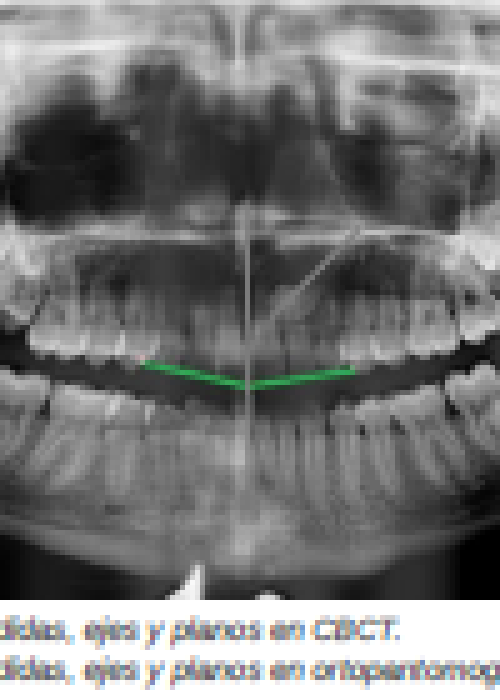

Diagnóstico radiográfico de los caninos maxilares incluidos. Comparación entre dos y tres dimensiones